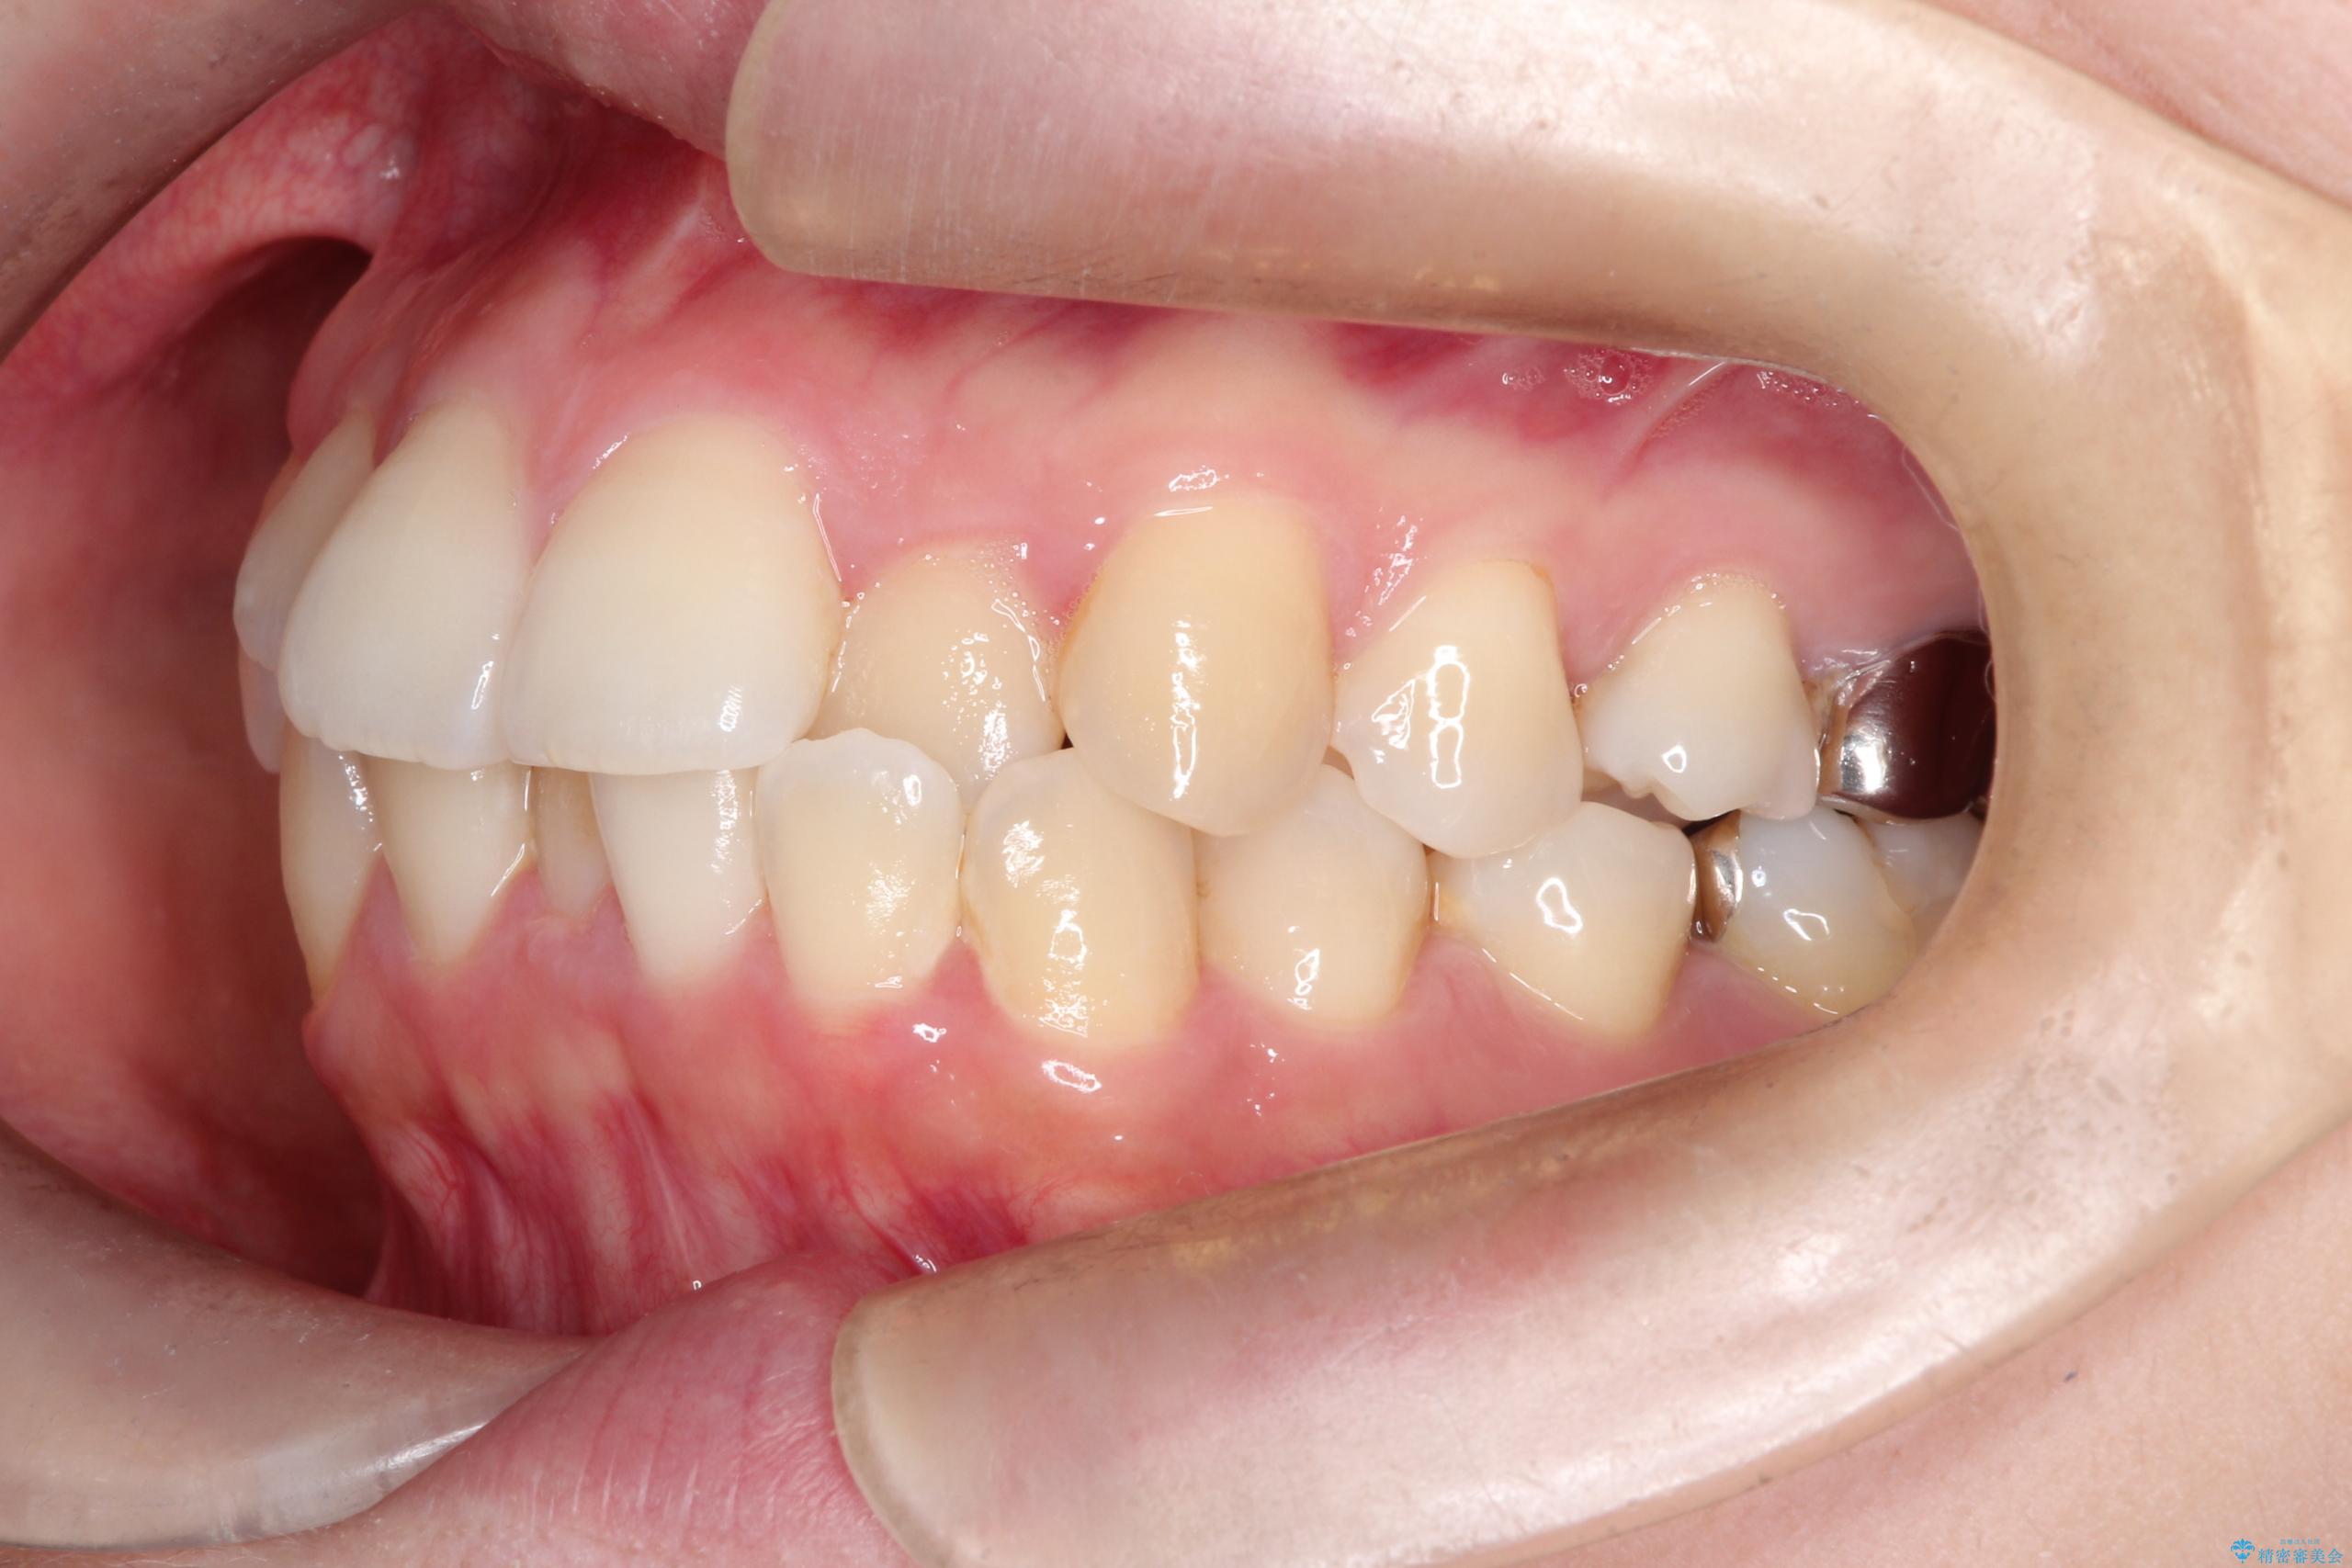

- 主訴:口元を下げて前突感を無くしたい、下の歯の凹凸も無くしたい

右側第二小臼歯、左側第一小臼歯、下顎両側第一大臼歯を抜歯しワイヤ-矯正を行いました。

骨格的顎の変位を認めたため、顔貌に対しピッタリ上下の歯の正中を合わせることは難しいと説明し、上下左右計4本小臼歯を抜歯しワイヤー矯正治療を行いました。